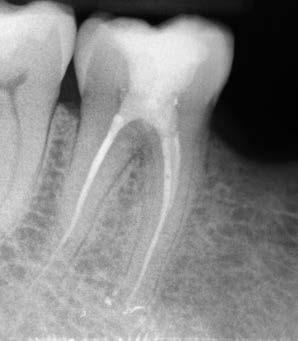

Egy 38 éves nőbeteg a korábban kezelt jobb felső második kisőrlőfogából (1.5) kiinduló mérsékelt fájdalom miatt jelentkezett rendelésünkön. A kórtörténetében jelen panasza szempontjából releváns információ nem szerepelt. A beteg a klinikai vizsgálat során vertikális kopogtatásra enyhe érzékenységet jelzett. A kérdéses fog körül mérhető szondázási mélység és a fogmobilitás fiziológiás volt. Periapicalis röntgenfelvételen egy, a fog gyökércsúcsán túl presszálódott betört gyökérkezelő műszerből származó eszközfragmentumot láttunk (2. a. ábra). A preoperatív CBCT-felvétel a buccalis csontlemez épségét igazolta (2. b-c. ábra). A fog revíziója öt hónappal korábban történt. A már előzőleg gyökérkezelt, gyökértömött, majd revideált 1.5-ös fog esetében a diagnózisunk periodontitis periapicalis symptomatica volt. A periapikális elváltozás kezelése érdekében navigált endodonciai mikrosebészeti beavatkozást végeztünk.

a-m. ábrák: Preoperatív röntgenfelvétel (a) és preoperatív CBCT-felvétel a jobb felső 5-ös (1.5) fogról, sagittalis (b) és axialis (c) nézetek. Az intraorális szkennelés során kapott STL-fájl (d). A 1.5-ös fog navigált endodonciai mikrosebészeti beavatkozásához tervezett sablon (e). A 1.5-ös fog navigált endodonciai mikrosebészeti beavatkozásához nyomtatott sablon (f). Teljes vastagságú mucoperiostealis lebenyt emeltünk (g). A sablont a helyére illesztettük, és a csontablak határait jelöltük (h). A fog gyökerén kívül eső, betört eszköz a 1.5-ös fog periapicalis régiójában (i). Az eltávolított betört eszköz (j). A rezekció, retrográd preparáció és a TotalFill BC RRM Fast Set Putty anyaggal elkészített retrográd gyökértömés utáni röntgenfelvétel (k). A lebenyt varratokkal rögzítettük (l). A kétéves kontroll során készített röntgenfelvétel (m).

gítségével tovább módosítottuk. Az így kapott sebészi sablon egyértelműen meghatározta a periapikális terület eléréséhez szükséges csontablak határait (2. e-f. ábra) Helyi érzéstelenítést követően teljes vastagságú mucoperiostealis lebenyt képeztünk, majd a buccalis csont feltárását követően (2. g. ábra) a sablon segítségével bejelöltük a preparálandó csontablak határait (2. h. ábra). A csontablak kialakítása során Piezotome CUBE LED kézi-darabot alkalmaztunk, majd a leemelését követően a betört eszközt megkerestük (2. i. ábra) és eltávolítottuk (2. j. ábra). A rezekciót ultrahangos megmunkáló fejekkel (ACTEON) végeztük, majd retrográd preparáció következett.

A retrográd gyökértömés elkészítése során TotalFill BC RRM Fast Set Putty-t (FKG) használtunk (2. k. ábra). A lebeny széleit 5/0-s Prolene varratokkal egyesítettük (2. l. ábra). A varratok a műtétet követően 72 órával kerültek eltávolításra. A beteg két évvel később kontrollröntgen készítése céljából érkezett rendelőnkbe. A vizsgálat során a fog tünetmentesnek és funkcióképesnek bizonyult (2. m. ábra).